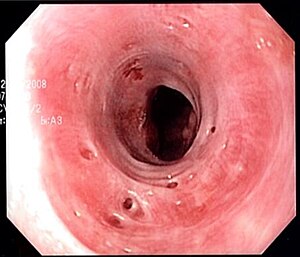

Endoscopic image of esophageal intramural pseudodiverticulosis demonstrating the flask-like outpouchings of the esophageal wall.

Endoscopic view of esophageal intramural pseudodiverticulosis revealing several small orifices

Esophageal intramucosal pseudodiverticulosis is typically diagnosed at the time of endoscopy of the esophagus. Endoscopy shows evidence of the pseudodiverticulae, which are typically numerous, appear like pits in the wall, and may be preferentially located in the upper esophagus.[2][4] The mucosal lining of the esophagus may be inflamed, and this can be seen on endoscopy or on biopsy; the mucosa, however, may also be normal if esophagitis is not the cause of the pseudodiverticulosis. The condition must also be excluded from esophageal cancer, which may be done at the time of endoscopy, or which may require esophageal biopsy.[2]